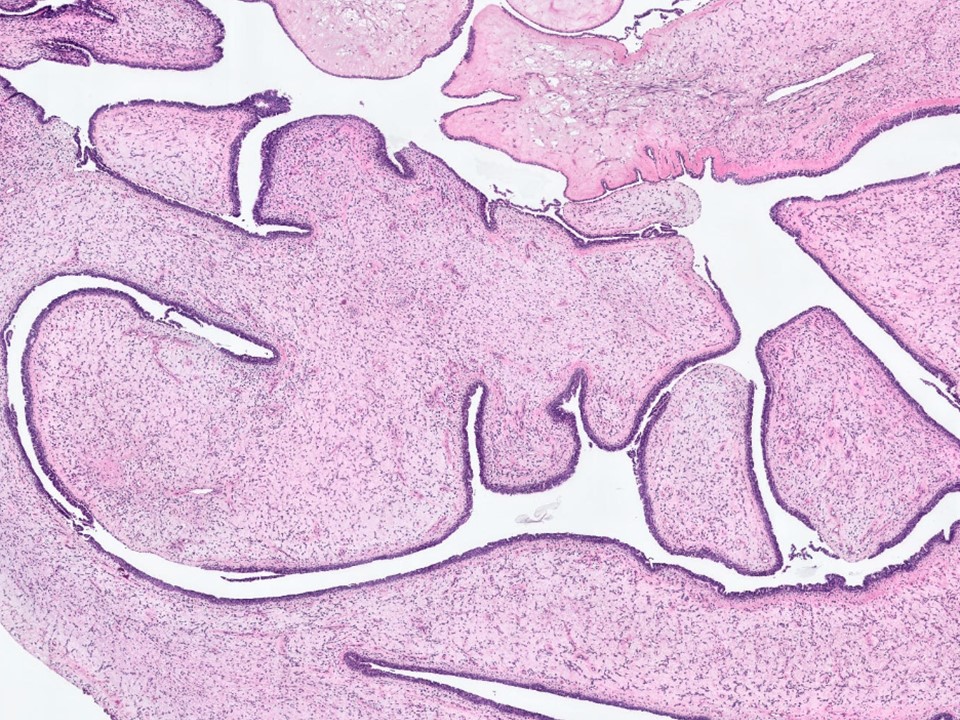

Intraductal Papilloma